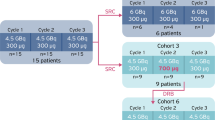

Following on from the Bad Berka study [7], ITM has initiated a Phase III pivotal clinical trial. COMPETE is a prospective, randomised, open-label multi-centre Phase III study to evaluate the safety and efficacy of 177Lu n.c.a.-edotreotide in comparison to everolimus in patients with G1 and G2 GEP NETs. The patients have progressive, somatostatin receptor (SSTR) positive disease on SSTR imaging. Uniquely, patients may be included as first-line therapy. There are 3 sub-studies which focus on 177Lu-edotreotide dosimetry and pharmacokinetics. These sub-studies are of great importance in the development of a personalised, precision therapy approach to the management of patients with PRRT. In addition, 177Lu is uniquely non-carrier-added, which means that it is a pure radionuclide of high specific activity.

The study is ongoing with a target recruitment of 300 patients. A total of 200 patients will receive 4 cycles of 177Lu-edotreotide (7.5 GBq/cycle) every 3 months or until disease progression and 100 patients will receive everolimus 10 mg daily for 24 months or until disease progression. The study duration is 24 months with 5 years follow-up for OS. The primary end-point is PFS as assessed by RECIST 1.1. Key secondary end-points include safety and tolerability, dosimetry, ORR, OS and quality of life (Fig. 13.5). Patients with G3 neuroendocrine neoplasms (Ki-67 > 20%) have more aggressive disease than the G1 and G2 NETs. In 2017, the WHO subdivided G3 NENs into well-differentiated G3 neuroendocrine tumours (NETs) and poorly differentiated neuroendocrine carcinomas (NECs) [11]. A retrospective study of PRRT in G3 NENs has been reported by Professor Baum’s group in Bad Berka [12]. Sixty-nine patients were treated with either 177Lu- or 90Y-labelled somatostatin analogues (DOTATATE or DOTATOC). This was a heterogeneous group of patients both in terms of disease and treatment. Overall, the median PFS was 9.6 months and the median OS was 19.9 months. When the patients were sub-into grouped into NETs with a Ki-67 index of ≤55%, the median PFS was 11 months and the OS 24 months. For NECs with a Ki-67 index of ≥55%, the median PFS was 4 months and the median OS was 7 months. In the patients who had positive SSTR imaging but negative 18F-FDG uptake, the prognosis was dramatically better. Other retrospective studies have also reported beneficial responses to PRRT in G3 NEN, particularly those with a Ki-67 index of ≤55% [13,14,15]. These low-grade G3 NETs are of particular interest for further clinical development. The high-grade G3 NECs (Ki-67 ≥ 55%) respond relatively poorly to PRRT. These tumours might benefit from combination therapies, particularly with DNA repair enzyme inhibitors.